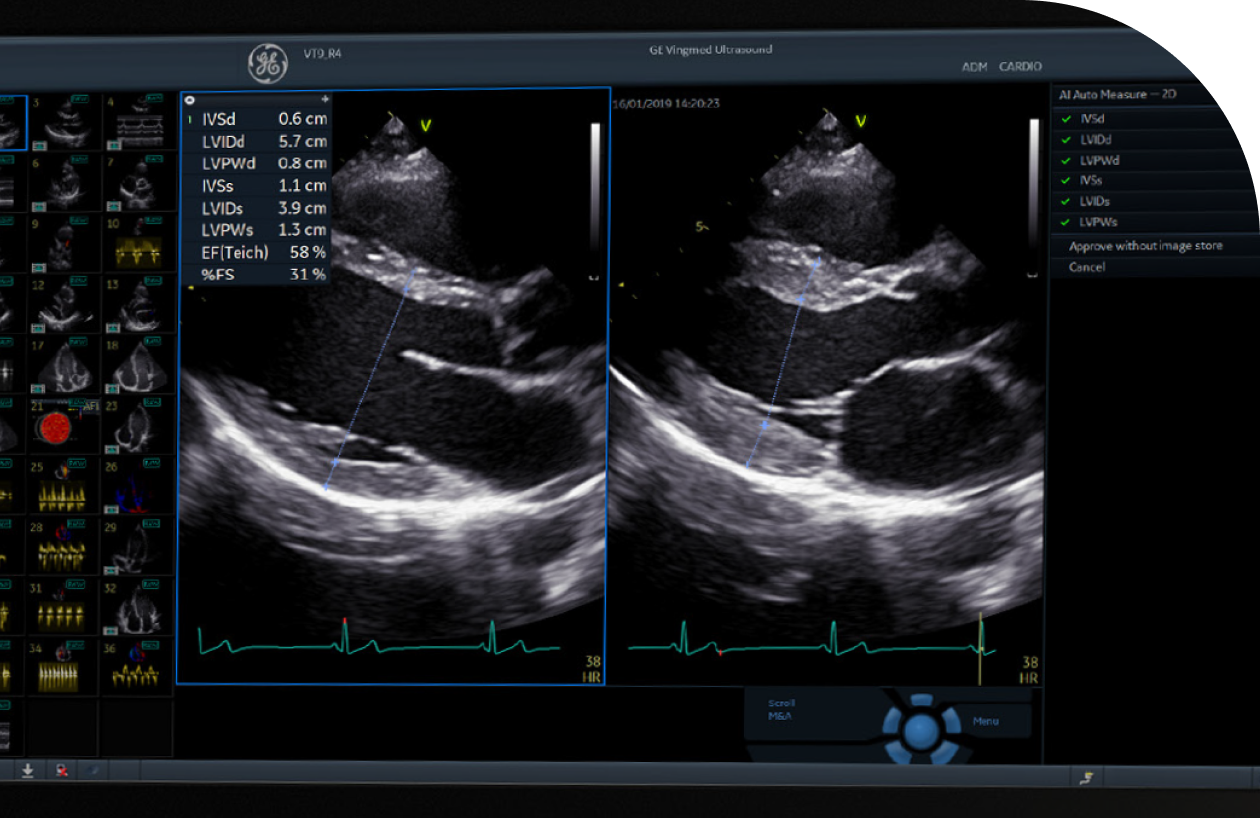

심장초음파

경험이 풍부한 심장전문의에 의한

실시 및 판독이 중요합니다

• 심장 기능, 구조적 이상, 판막 이상, 심장 확장 및 비대 등을 정확히 진단

• 환자는 옆으로 누워 앞가슴과 옆가슴에 젤을 바르고 초음파로 심장 움직임 관찰